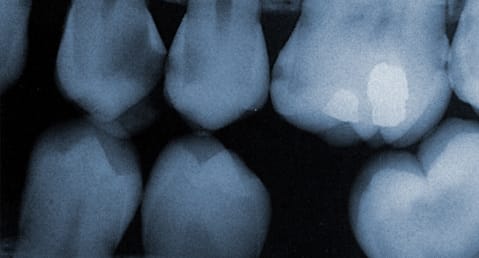

a few teeth showing in a dental x-ray

It is recommended to have a full set of dental x-rays taken once a year during a regular dental checkup. Most dental insurance plans will cover the cost of x-rays taken once a year and should not be skipped out on. Dental x-rays will expose any problems that might be currently present and can be used to prevent problems that may occur in the near future. Tooth roots, jaw bone and sinuses are all visible with a quick x-ray which allows us to detect problems with the bone surrounding teeth and even allow us to see teeth that have not erupted such as permanent teeth in children or wisdom teeth in adults.

We use modern digital x-rays that use an extremely low level of radiation to create an x-ray. Digital x-rays also eliminate x-ray films from having to be developed which also minimizes the time you spend in our dental chair.